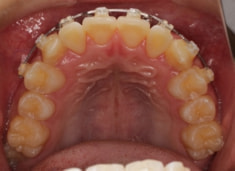

治療法:上顎急速拡大装置+クリアスナップ+フェイスマスク+上顎3番は開窓牽引CT写真にて位置確認

(難症例のため、小児期の矯正を2段階に設定しました)

上下顎のギャップはありますが、顔面自体の幅径は良好な値を示していますので、スペース不足は拡大することによって解決できポテンシャルはあると考えられます。

検査時のレントゲン分析では、上下顎の関係は、上顎の劣成長があり下顎前突傾向という値がでておりましたが、前歯ジャンプ後はフェイスマスクの効果もあり、上下顎の関係は正常化しています。